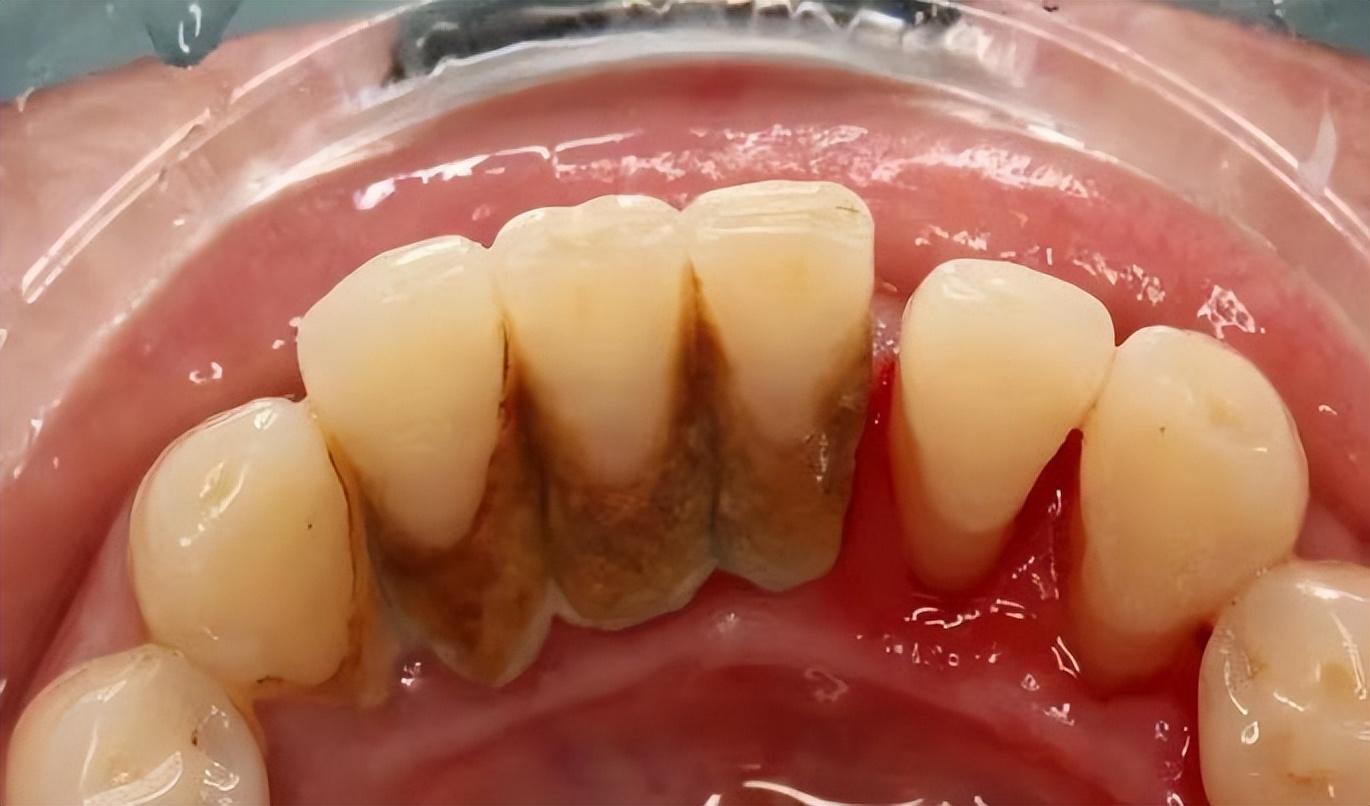

牙结石

这些会让你的牙齿看起来脏脏的,口腔有异味,并且会让牙龈生病!